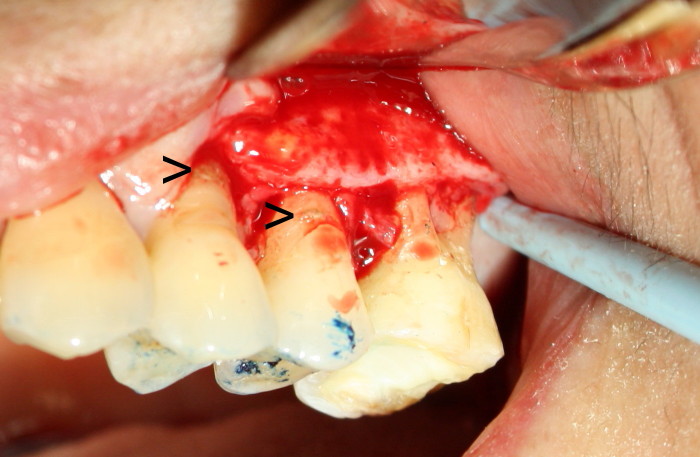

图七放大:翻瓣后,显示龈下结石(箭头),回